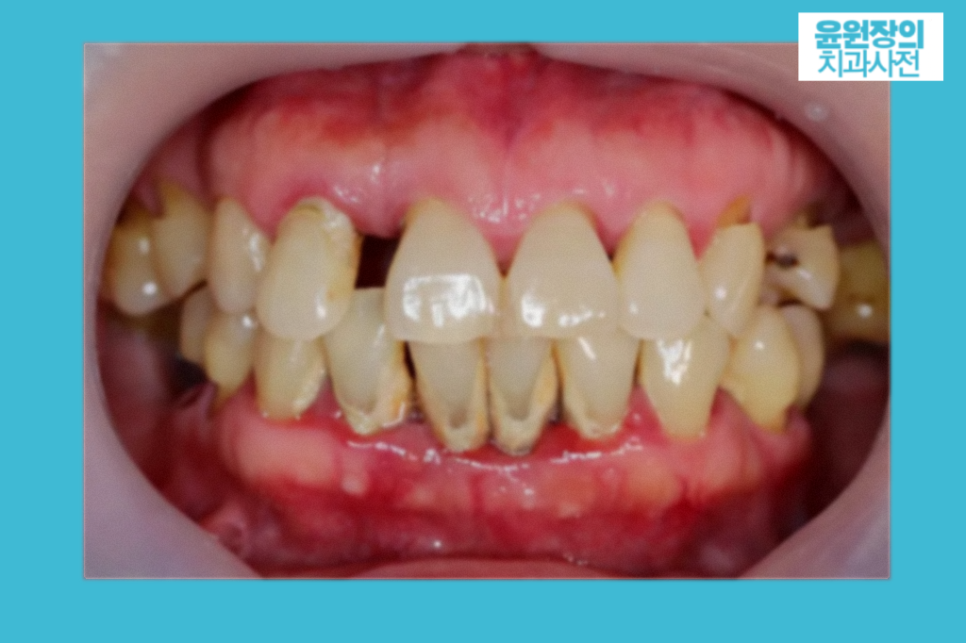

그러면 잇몸이 욱신거리는 경우는 어떤 경우일까요?

치주염이라고 혹시 들어보셨나요?

말그대로 치주(잇몸)에 염증이 생긴 건데요,

감기와 더불어 우리나라에서 많이 발병하는 질환 중 하나입니다.

그만큼 여러분도 이미 가지고 계실 가능성이 크다는 뜻입니다.

치주염은 보통 잇몸이 붓거나, 치아가 들뜬 듯한 느낌이 듭니다.

잇몸욱신, 즉 치주염의 경우에는 스케일링같은 잇몸치료를 받으셔야 합니다.

잇몸에 치석이나 치태가 원인이니까요.